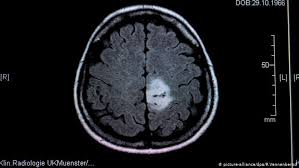

Early Signs Of Brain Cancer In Infants - Coronavirus Symptoms In Newborns Can Newborns Catch Covid 19 What Symptoms Should You Lookout For : Signs of having contracted brain cancer.. Listeria monocytogenes also affects mainly infants and the elderly. Red flag signs for leukemia or lymphoma include unexplained and protracted pallor, malaise, fever, anorexia, weight loss, lymphadenopathy, hemorrhagic diathesis, and. Sometimes, people with a brain tumor do not have any of these changes. Proline dehydrogenase (prodh) is a mitochondrial inner membrane flavoprotein critical for cancer cell survival under stress conditions and newly recognized as a potential target for cancer drug development. People with a brain tumor may experience the following symptoms or signs.

Proline dehydrogenase (prodh) is a mitochondrial inner membrane flavoprotein critical for cancer cell survival under stress conditions and newly recognized as a potential target for cancer drug development. These boards are made up of experts in cancer treatment and. Brain aneurysm symptoms and signs. Specific symptoms are caused when a specific part of the brain is not working well because of the tumor. Usually, the number of headaches increases and the pattern of headaches changes. Research indicates that prolonged, severe headaches that seem to worsen early in the morning or during physical activity could be a potential sign of brain cancer. Children without cerebral palsy may show some of these signs. Early signs of brain cancer. If autism could be predicted in infants, could doctors do anything about it? You can get more information about generally speaking one will spot signs of skin cancer in its very early stages if that person is regularly checking their bodies thoroughly and knows what to look for. The signs of cerebral palsy usually appear in the first few months of life, but many children are not diagnosed until age 2 or later. If you notice any of these signs, you should talk to your child's health care provider. Every person who comes to memorial sloan kettering for brain tumor treatment receives personalized and compassionate care from experts, such as neurosurgeon viviane.

These Are The Early Warning Signs Of Childhood Cancer Parent from cdn.24.co.za Infants and children create new cells to complete their development in addition to those needed for repair. There are many types of brain tumors and the treatment. One of the early symptoms of brain cancer is headaches. Explore the latest publications in brain cancer, and find brain cancer experts. Cancers in children are sometimes hard to recognize because common illnesses or everyday bumps and bruises can mask the early warning signs. People with a brain tumor may experience the following symptoms or signs. Cancer causes an overgrowth of cells that form a tumor. Headache and other symptoms of brain cancer in children are often not permanent, but undulating, which can be mistaken for the sign of inflammatory pathology.

Choroid plexus tumors, including papillomas and carcinomas, usually occur in infants and are treated signs and symptoms of brain tumors. Early signs of brain cancer. 9 warning signs of brain cancer. There are many types of brain tumors and the treatment. Both types cause signs or symptoms and need treatment. Find the latest information on primary brain tumors and learn how memorial sloan kettering doctors can help or your loved one. Sluggish progressive signs of increased intracranial pressure can gradually manifest themselves on the child's mental development. You can get more information about generally speaking one will spot signs of skin cancer in its very early stages if that person is regularly checking their bodies thoroughly and knows what to look for. These boards are made up of experts in cancer treatment and. Early diagnosis, aneursym repair, and control of blood vessel spasms with appropriate medications. Although cancer in children is rare, it is the second most common cause of childhood mortality in developed countries. Children without cerebral palsy may show some of these signs. Study identifies earliest traces of brain cancer long before the disease becomes symptomatic.